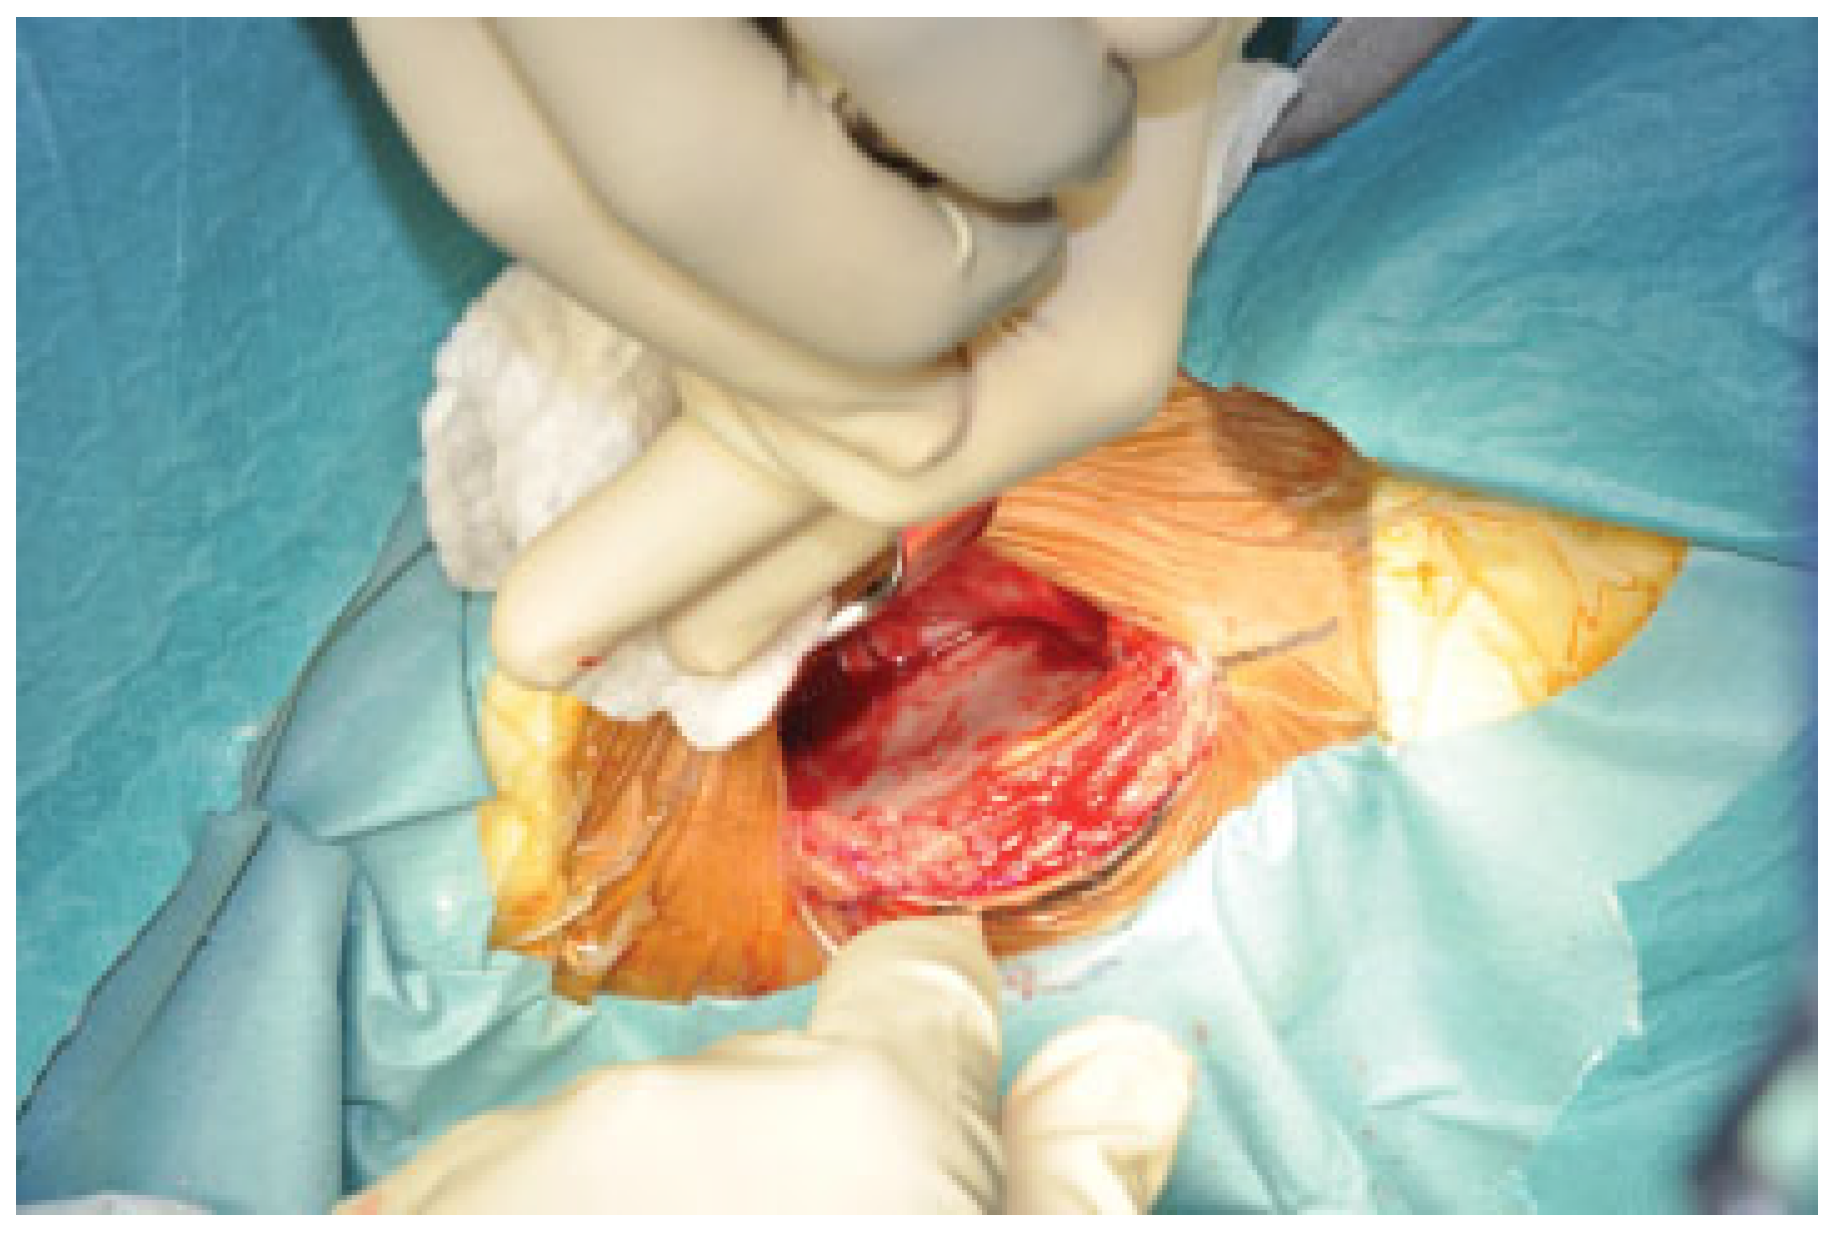

Surgical Technique